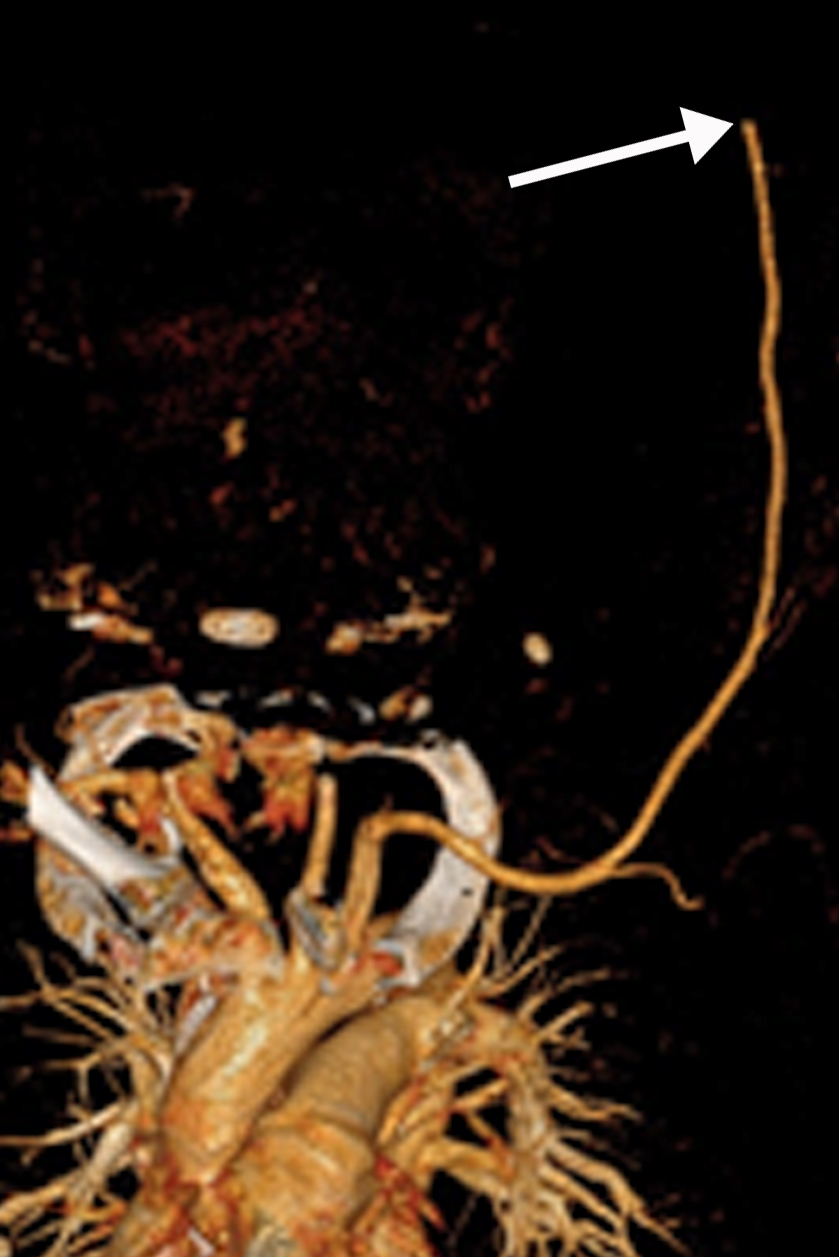

This photo gallery shows the variety of radiological presentations of COVID-19 (SARS-CoV-2) in medical imaging, including computed tomography (CT), radiograph X-rays, ultrasound, echocardiograms and magnetic resonance imaging (MRI). The radiology images show examples of typical COVID pneumonia in the lungs and the numerous complications the virus causes in the body in multiple organs, including the brain, kidneys, heart, abdomen and vascular system.

Ultrasound, especially hand-held ultrasound imaging devices, have become a primary imaging modality for novel coronavirus because of the ease to bag the device and sterilize it after use. CT and mobile X-ray systems are also used as front-line imaging systems for COVID-positive or suspected COVID patients.